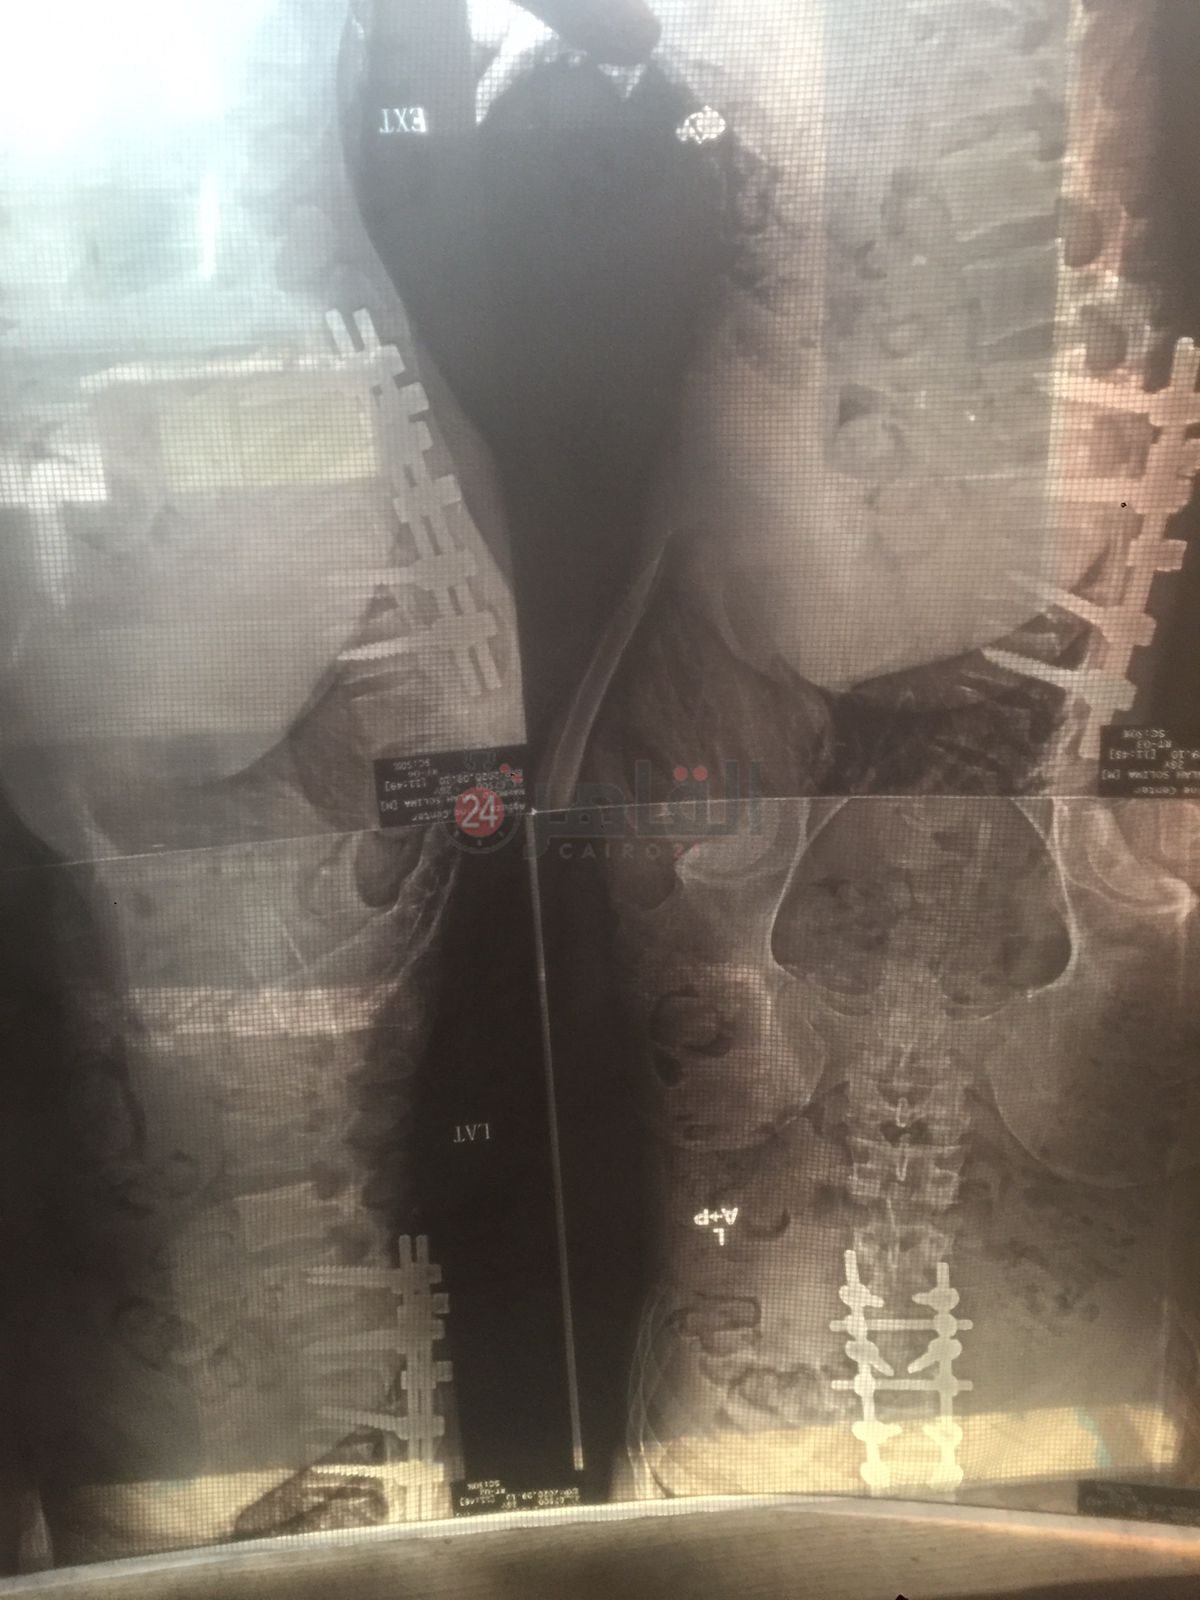

وتابع صلاح: كنتٌ أعمل بإحدى شركات الخدمات البترولية، وسقط عليّ 2 طن حديد، مما أدى إلى كسر الفقرة القطنية، مع الضغط الشديد على النخاع الشوكي، الأمر الذي أدى إلى إصابتي بضمور العضلات.